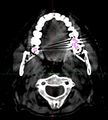

Eksempel på artefakter fra tandfyldninger.